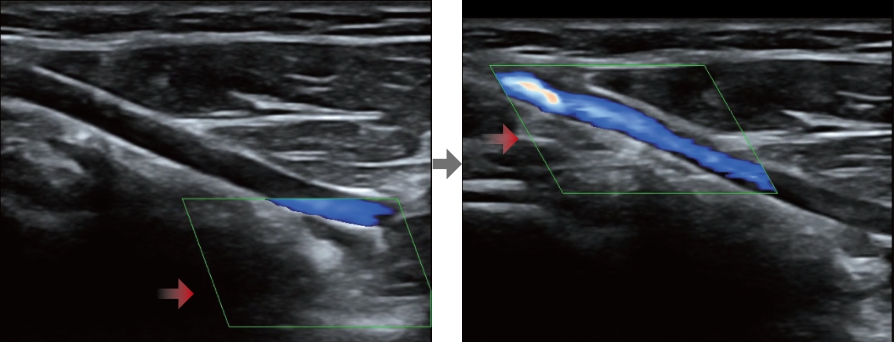

Smart Track

Smart Track proporciona una optimizaciĂłn rĂĄpida e inteligente de imĂĄgenes vasculares con un sencillo manejo de un solo toque. Puede optimizar el espectro de Color, Potencia y PW mediante seguimiento automĂĄtico y reducir los pasos que llevan tiempo. Por lo tanto, el flujo de trabajo del examen vascular se simplifica con una Ăłptima visualizaciĂłn.